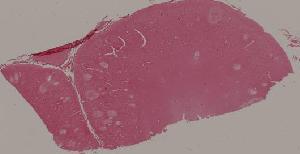

94. Encephalitis type B